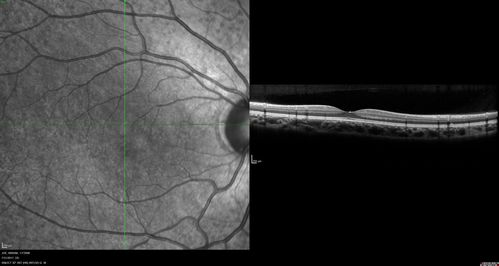

Fundus Albipunctatus

12 year old female with normal vision. She has 4 siblings all of whom have either white spots or spots on IR. Genetic testing by parents was deferred.